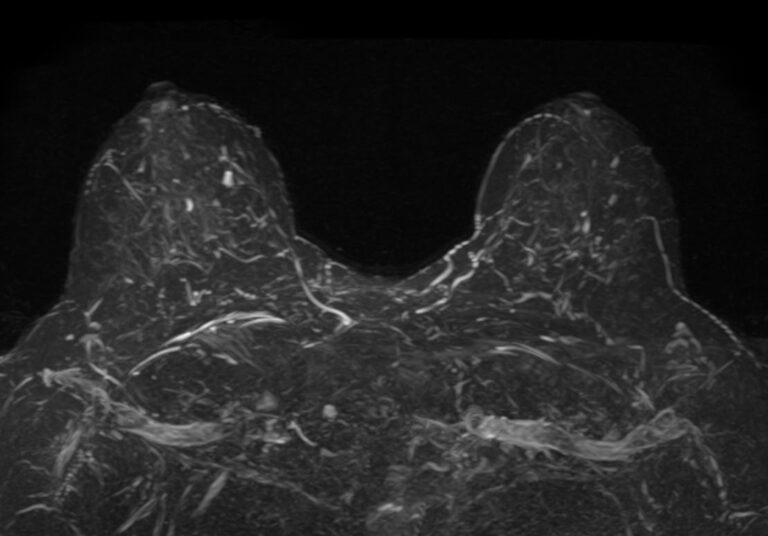

Выполнение МРТ молочных желез без контрастирования возможно для динамического наблюдения состояния имплантатов после пластической операции груди. Во всех остальных случаях во время проведения исследования внутривенно вводится контрастное вещество. Для контрастного усиления применяются препараты на основе солей гадолиния (Магневист, Гадовист и др).

Полученные во время исследования результаты сканирования при помощи компьютерной программы преобразуются в 3D-изображения, что дает детальную информацию о состоянии молочных желез и регионарных лимфоузлов.